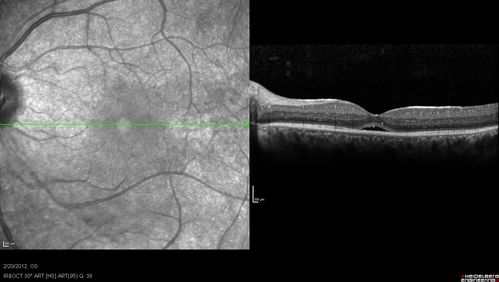

Retinitis Pigmentosa Sine Pigmento or Unknown Dystrophy - Peripheral Superficial White Spots and Recurrent CME

1 month of treatment with diamox 500 mg BID- cme is a little better